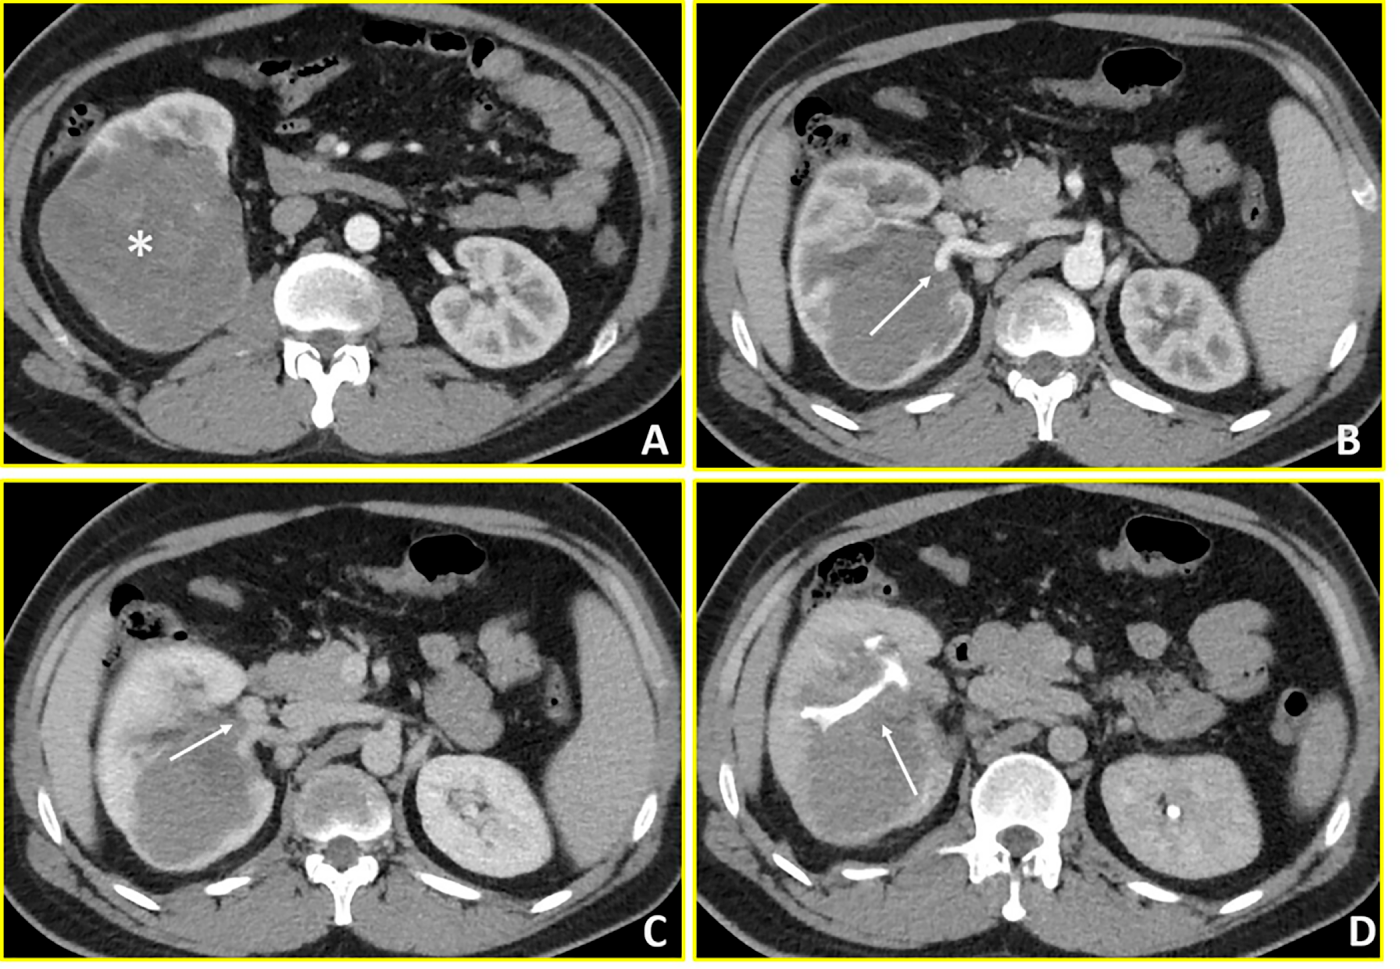

A 15-year-old male presented to the Emergency Department of Policlinico Gemelli with gross haematuria. Initial abdominal ultrasonography revealed a right renal lesion, subsequently confirmed by contrast-enhanced abdominal CT and MRI as a 13 × 8 × 9 cm neoplasm with infiltration of the renal pelvis, involvement of hilar vessels (both renal artery and vein), and direct contact with the ipsilateral adrenal gland (Fig. 1). Thoracic CT demonstrated no metastatic disease. Following multidisciplinary tumour board discussion (including oncologist, urologist and radiologist), the decision for upfront surgery was made based on the patient aged 15 years and 8 months approaching the 16-year protocol threshold combined with high-risk radiological features: extensive hilar vascular infiltration, intraparenchymal extension with renal pelvis involvement, and immediate risk of complications including haemorrhage or rupture as recognized by SIOP-RTSG guidelines for tumour-related emergencies. The patient underwent immediate video-laparoscopic right nephroureterectomy with adrenalectomy, performed en-bloc to ensure disease-free surgical margins given the intimate tumour-adrenal anatomical relationship demonstrating concern for adherence on imaging. The patient subsequently received post-operative chemotherapy according to the SIOP-RSTG Umbrella protocol. Clinical and radiological surveillance with physical examination, abdominal ultrasound, chest X-ray, urine tests and blood tests were programmed every three months for the first two years, then continued every six months till the fifth year. No disease recurrence was observed after more than three years of follow-up.

Figure 1: Wilms’ Tumour (Case 1). Contrast-enhanced CT imaging demonstrates a hypovascular mass in the right kidney with extensive vascular and collecting system involvement. (A, B) Axial arterial-phase images reveal a predominantly hypovascular renal mass (asterisk) with infiltration of the right renal artery (arrow in B). (C) Axial venous-phase image shows tumor extension into the right renal vein (arrow). (D) Axial urographic-phase image demonstrates infiltration of the renal collecting system with involvement of the renal calyces (arrow).